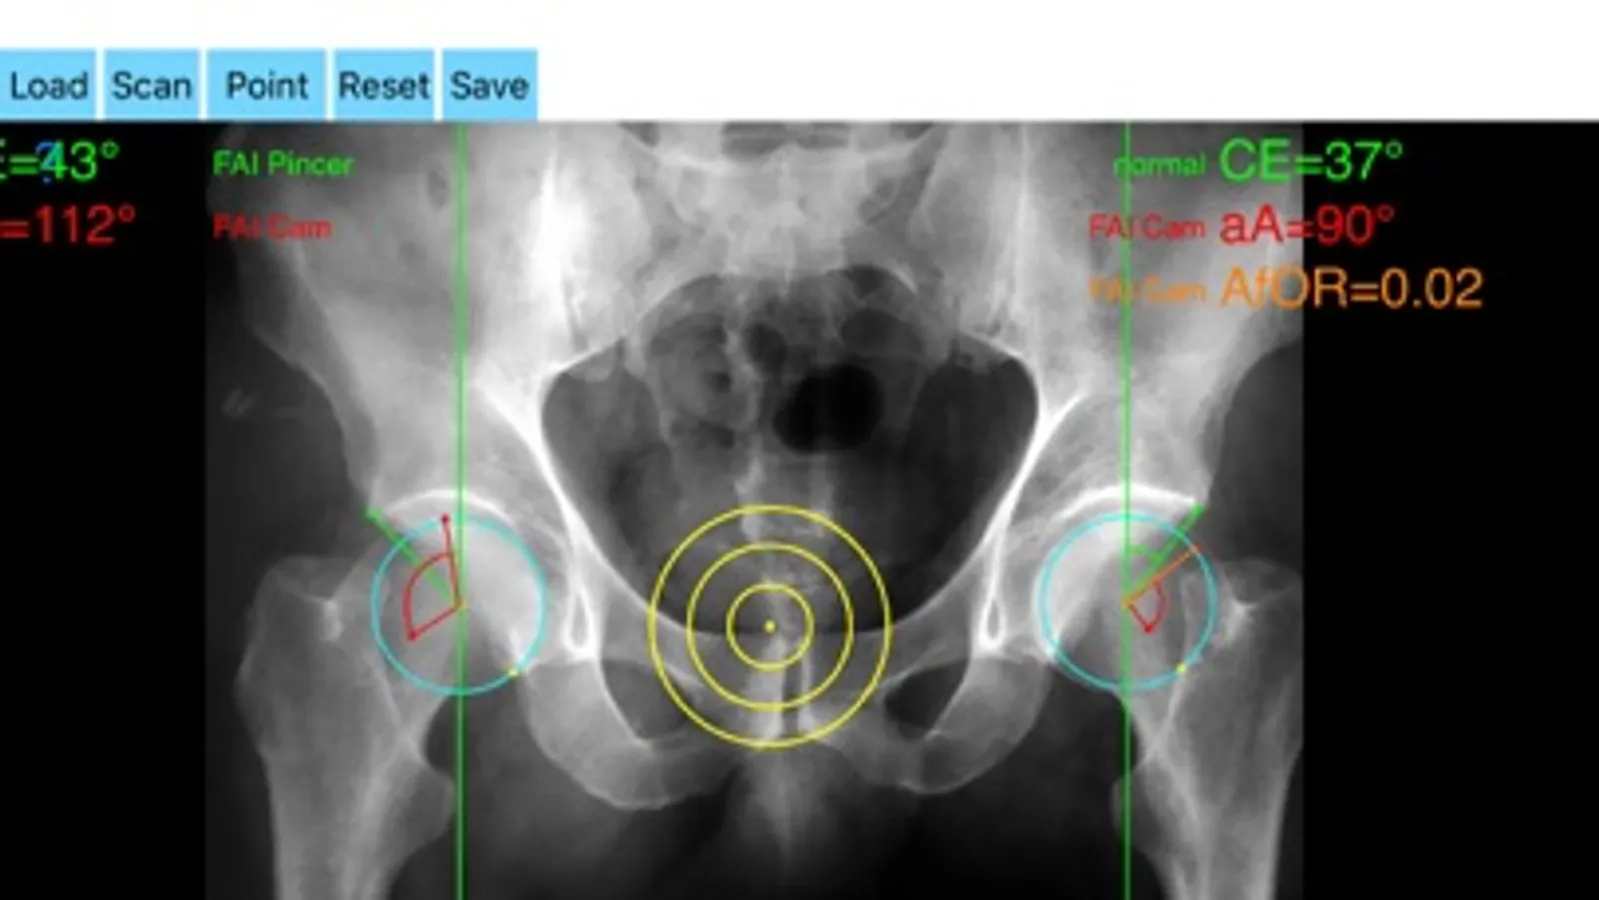

The drawn lines between points, allows app to estimate in radiographs, Center-Edge Angle (CE), α - angle (aA) and the anterior femoral offset ratio (AfOR). The measured values are compared with values from normal reference database. In case the measured angles are beyond the normal range, the hip is categorized as normal, dysplastic, borderline dysplastic hip and the type of femoroacetabular impingement (FAI) deformity namely cam type, pincer type or mixed is printed over the screen accordingly. Measures by the app are not affected by the X-ray projection.